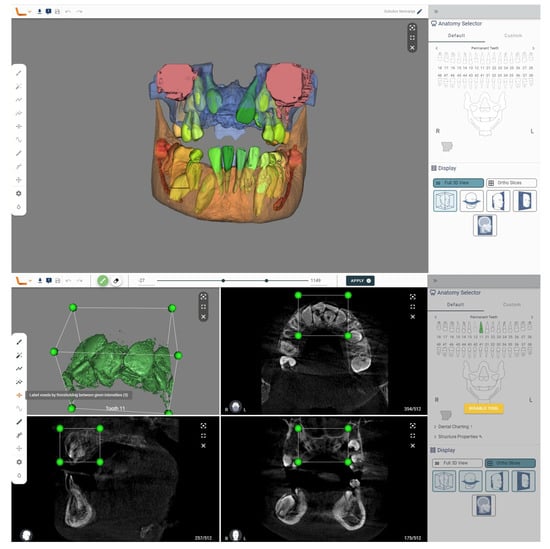

We analyzed a CBCT scan of the same patient using another tool, the Virtual Patient Creator (Relu, Leuven, Belgium). The tool did not recognize supernumerary teeth in the automatic analysis. But this tool offers numerous additional capabilities that can aid in diagnosing supernumerary teeth. After the initial segmentation, postprocessing steps can be applied to refine the segmented structures. By selecting the structure, in 2D cross-sections, a region can be identified for further analysis using the section labeled voxels by thresholding between given the intensities. This may involve removing outliers, smoothing the surface, filling gaps, or performing other operations to improve the accuracy and quality of the segmentation results. Once the segmentation is complete, the segmented structures can be visualized in 3D and further analyzed.

Figure 3.